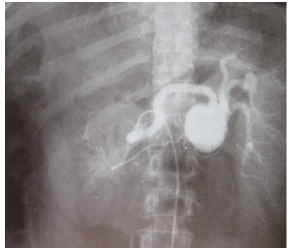

Paciente feminina, 34 anos, apresenta

dor abdominal em hipogástrio E há 2

anos, sem fatores de melhora ou piora

da dor. Dores esporádicas e de leve

intensidade. Sem comorbidades. Gesta

1. Como cirurgias prévias, apresenta:

Apendicectomia e cir. plástica de

mamas. Exame físico normal. Ao realizar

ecografia abdominal e arteriografia de

abdômen, obteve-se a seguinte imagem: